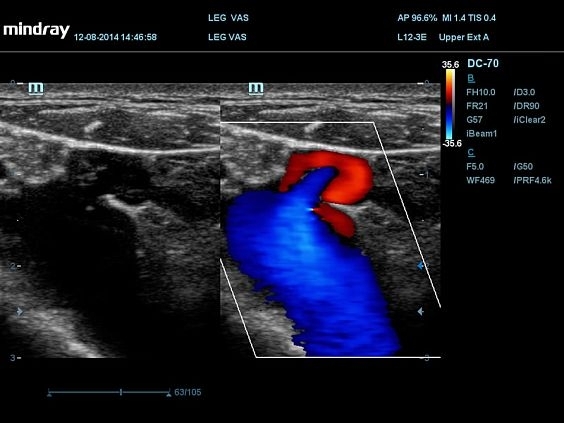

Изображения

Универсальные, Кардиологические, Гинекологические, Педиатрические, 3D/4D акушерство